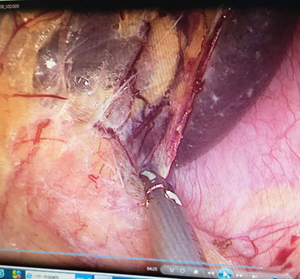

1. 腹腔镜肝切除

(1)沿缺血线解剖的半肝切除

(2)荧光腹腔镜肝切除

S6段反染